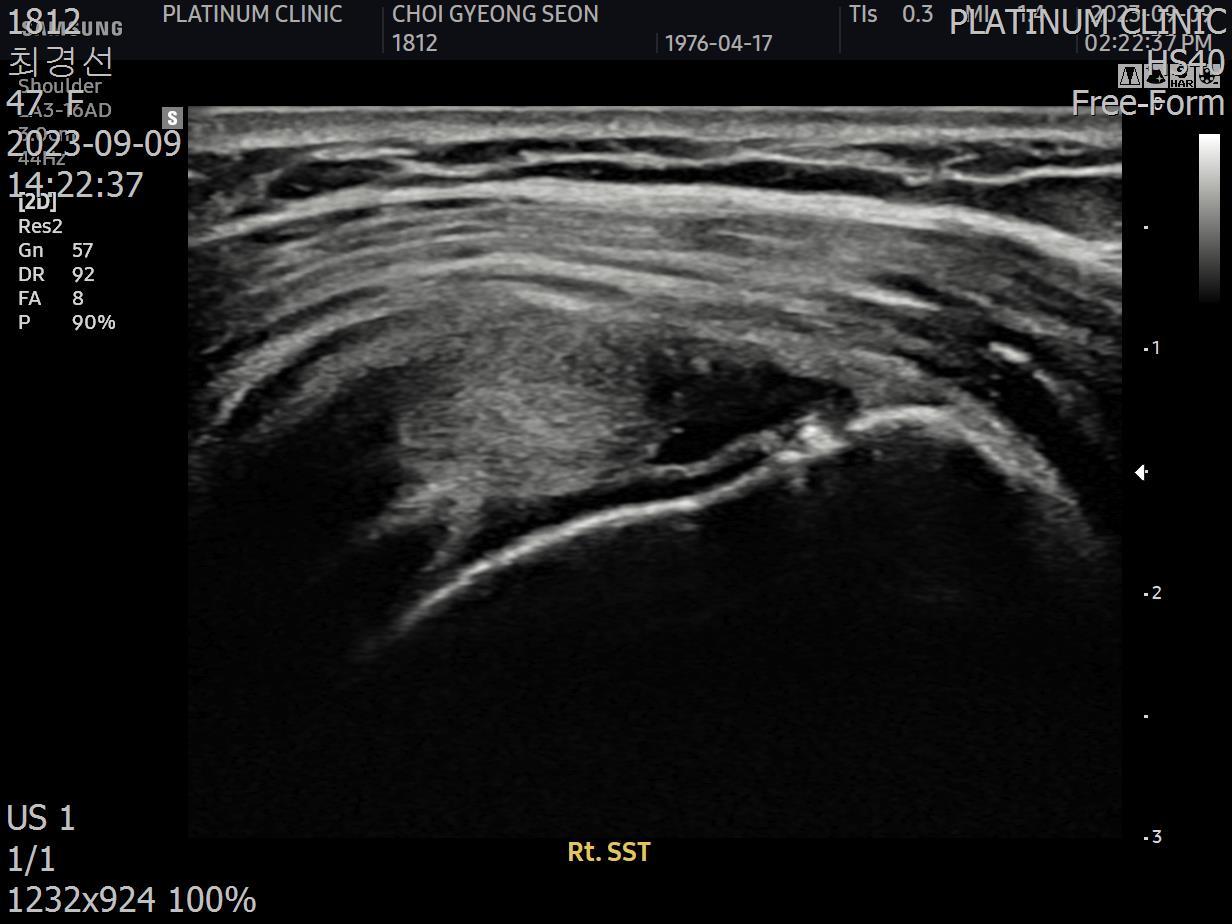

초음파 검사를 해보았습니다.

결과는 안타까웠습니다. 6개월 전보다 파열이 더 진행되어 있었습니다.

초음파 검사로 확인할 수 있습니다.

치료 전 초음파에서 검게 보이던 파열 부위가, 치료 후에는 정상 인대처럼 하얗게 보입니다. 이것이 구조적 회복의 증거입니다.

안 아파요"라는 주관적 느낌만으로 치료 완료를 판단하면 안 됩니다. 영상으로 확인된 구조적 회복이 있어야 진정한 치료입니다.

초음파 검사에서 손상 부위가 회복되었음이 확인되어야 합니다.

파열 부위가 재생되어 정상 에코(밝기)를 보임

인대 두께가 정상 범위로 회복됨

주변 염증 소견이 사라짐

초음파 결과:

이전에 검게 보이던 파열 부위가 하얗게 재생됨

주변 염증 소견 소실